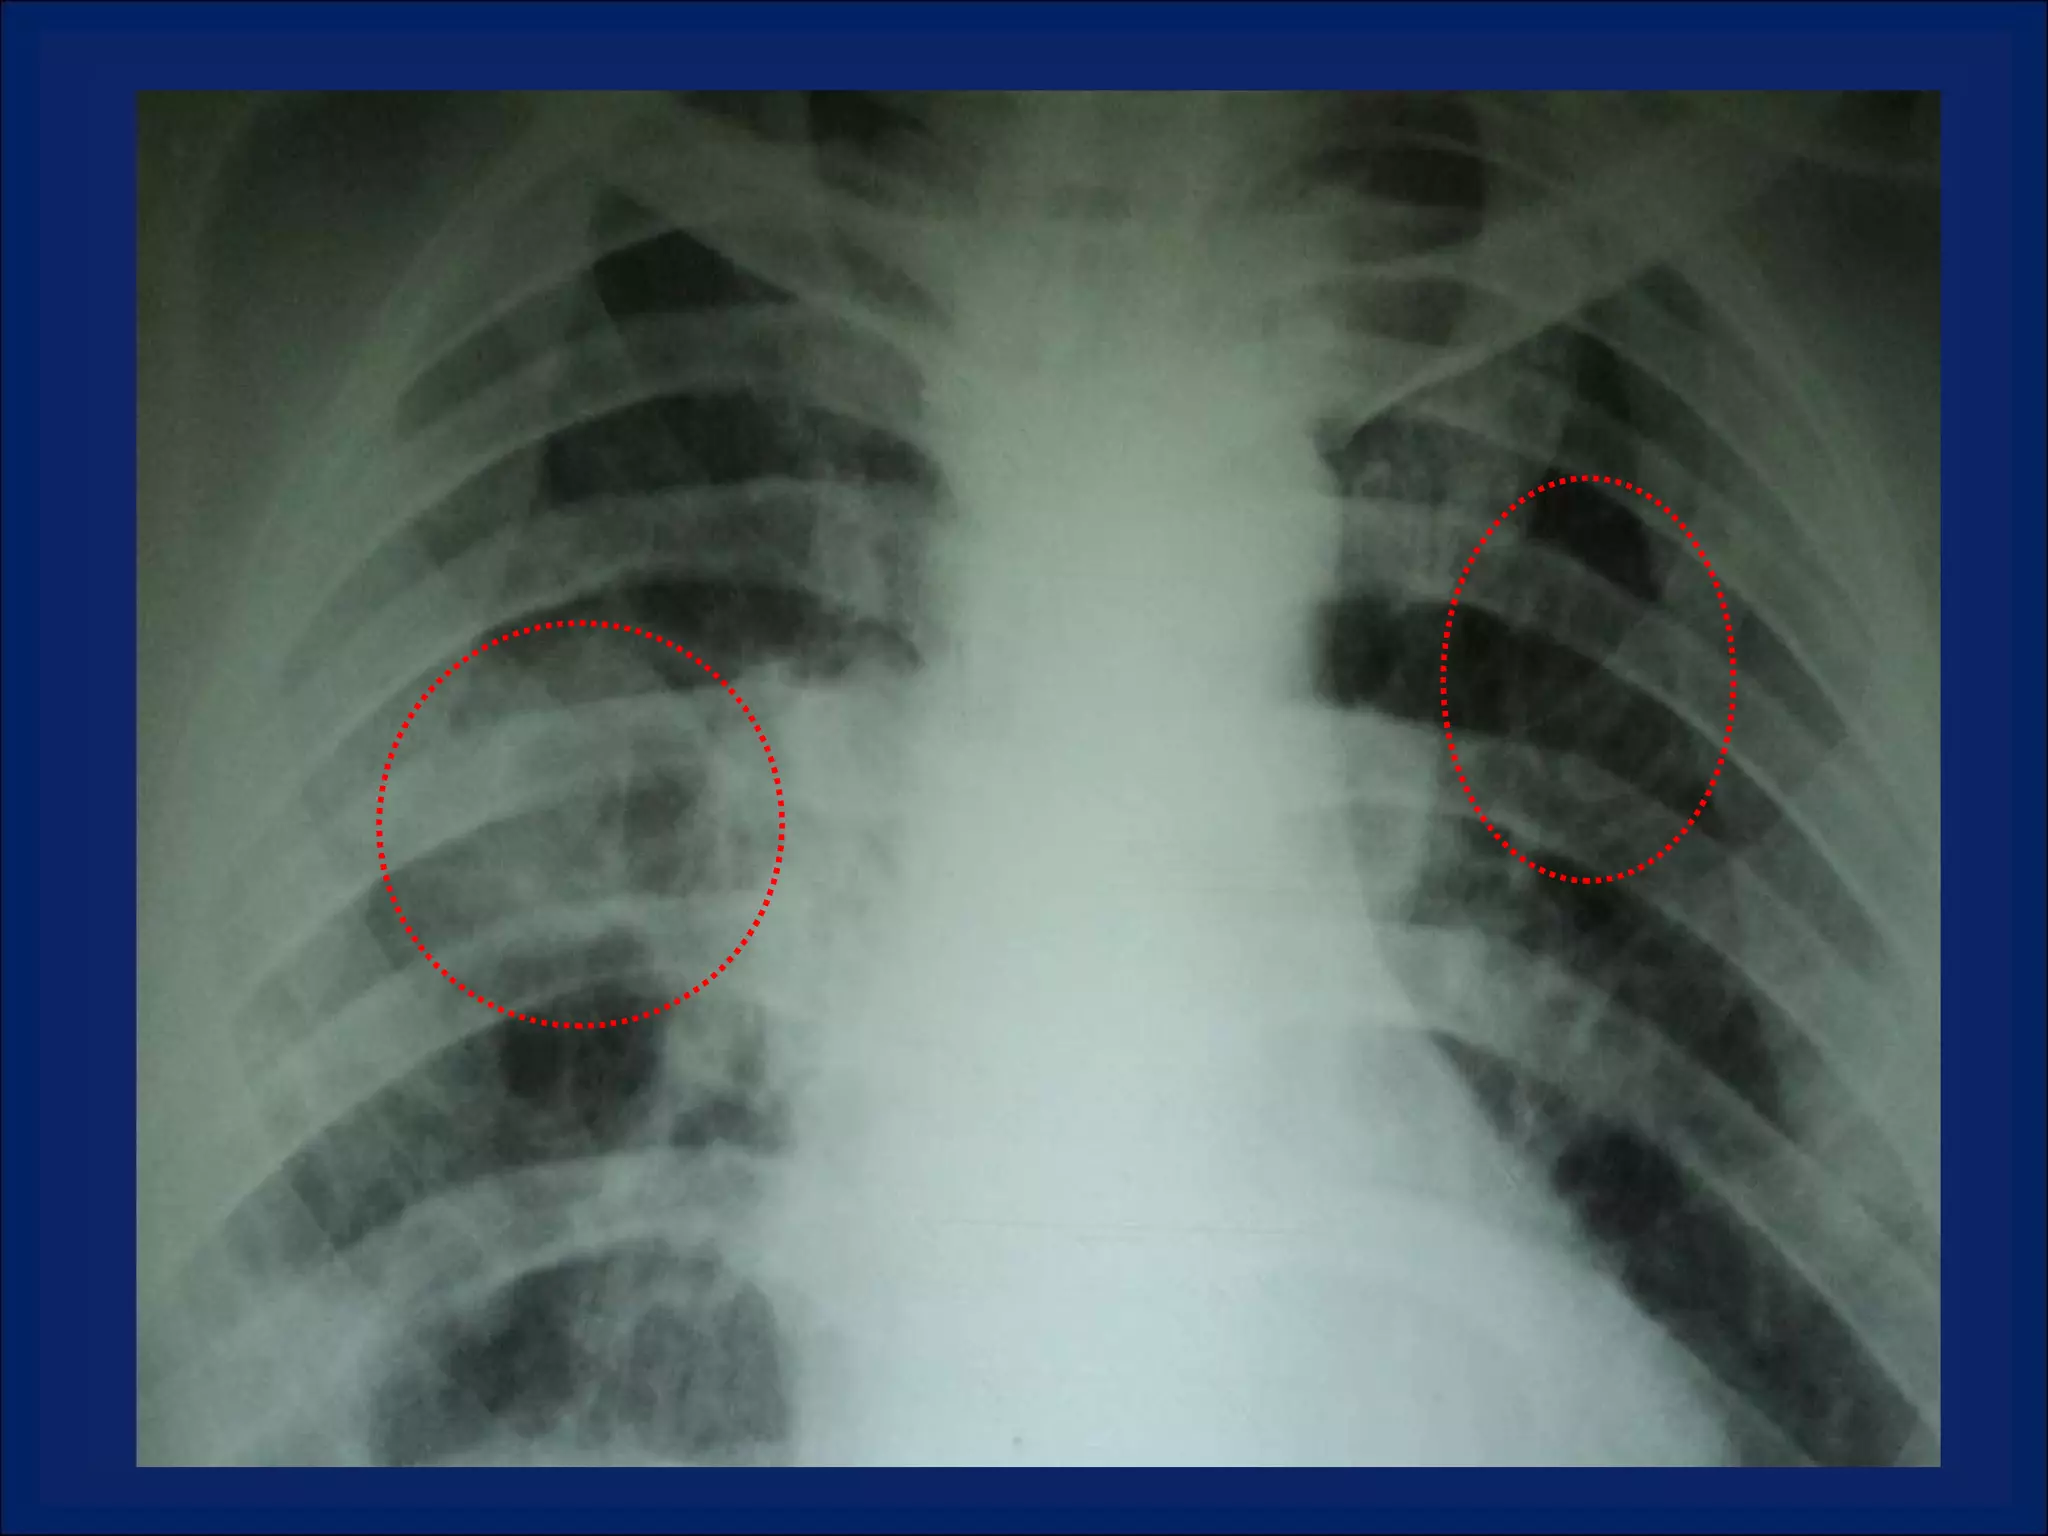

Imaging: Multiple Pulmonary Cavitary Lesions

LOOKING  AT  CAVITIES What is the anatomic distribution?  Is It single or multiple?  If multiple , are they focally located or diffusely seen in multiple lobes of both lungs? Is are the characteristics of the cavity? Is the cavity wall thick or thin? Is the interior lining nodular, shaggy, or smooth? Are there any other associated radiographic abnormalities?